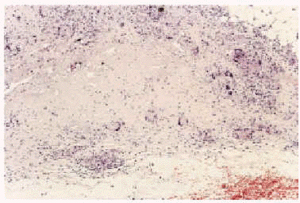

Realizamos biopsia de uno de los nódulos, que mostró la existencia en dermis profunda y septos hipodérmicos de amplias zonas de necrobiosis del colágeno (fig. 2), que formaban granulomas en empalizada rodeados por abundantes células gigantes multinucleadas (fig. 3), lo que llevó al diagnóstico de paniculitis septal por necrobiosis lipoídica.

Fig. 2.--Imagen histológica de una lesión nodular. Engrosamiento de los septos con focos extensos de necrobiosis que se extienden a la dermis reticular profunda.